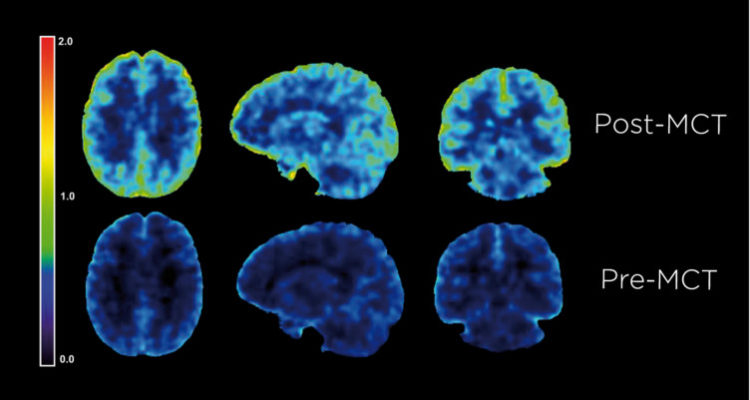

MCT v destilovanej forme majú unikátnu vlastnosť aktivácie tvorby ketónov, vďaka čomu viete efektívnejšie začať spaľovať tuky aj bez potreby dlhšej a náročnej adaptácie na tukový metabolizmus a nízkosacharidovú až ketogenickú stravu. MCT olej sa tak považuje za jeden z najefektívnejších zdrojov energie a doplnok výživy nie len pre telo, ale hlavne pre mozog. Jeho metabolická dráha je veľmi rýchla a bez záťaže žlčníka sa v pečeni konvertujú priamo na ketóny, ktoré za vybraných podmienok dokážu výborne dodať energiu pre mozog.

Zo súčasných nových poznatkov o metabolizme a ketónoch vyplýva, že ketóny sú efektívnejším zdrojom energie pre mozog ako glukóza. (Vid referencie dole)

Study Shows How Bulletproof Brain Octane C8 MCT Oil Powers the Brain